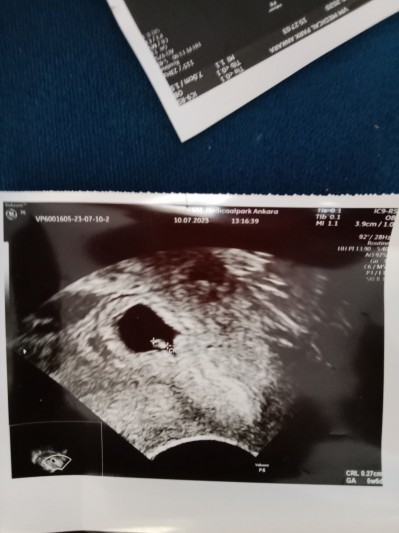

Oğlum bu haftada kesesi fasulye gibiydi bu kese bozuk mu ya sinirlerim bozuldu

image

Gebelik haftası 6

Sağlıksız olabilir falan dedi bekleyelim dedi ama benim içime sinmedi şehir Hastanesi'ne haftaya randevu alıcam ama sinirlerim çok bozuk ağrım sızım yok kese biçimsiz mi anlayamadım evet oğlumdan farklı ikisini yan yana koyunca ama herkeste değişmez mi ya

Daha yeni 6 hafta oldu kese şekli sizce sağlıksız mı ya

6ci Haftada bebek bu kadar net gözüküyor mu ya  ben gittim kese var bebek yok denildi

Alttan muayene bu karından göz0kmedi

canım.sağlıksız sa dusuyor zaten ama kese şekli doktorun cihazı karnında nsl tutugu bastirdigi önemli ona göre kese sekileniyir öyle kese şekli fasulyeymis yuvarlakmis kız çocuk erkek çocuk onlar hepsi asilsizdir